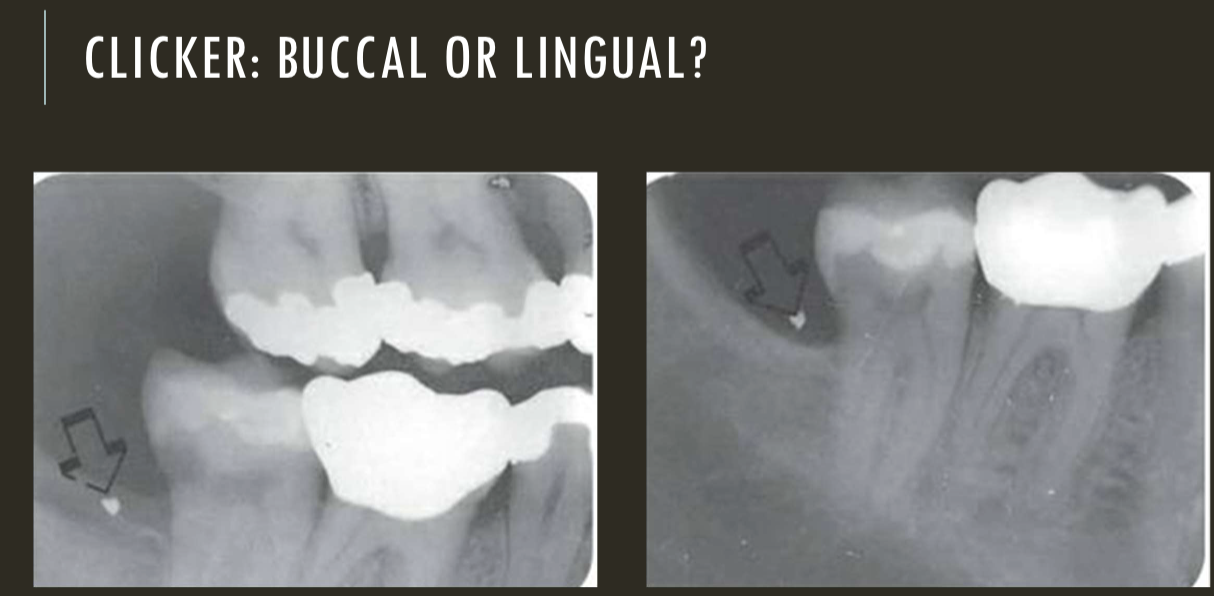

buccal object rule

expose 1st image (PA or bw)

take a second image with a different H or V angulation aka same area different angle

compare images to see how the object shifted in the image

SLOB

lingual

right angle technique

buccal

lingual

lingual

buccal

unable to assess from this single image the objects buccal-lingual position relative to the teeth